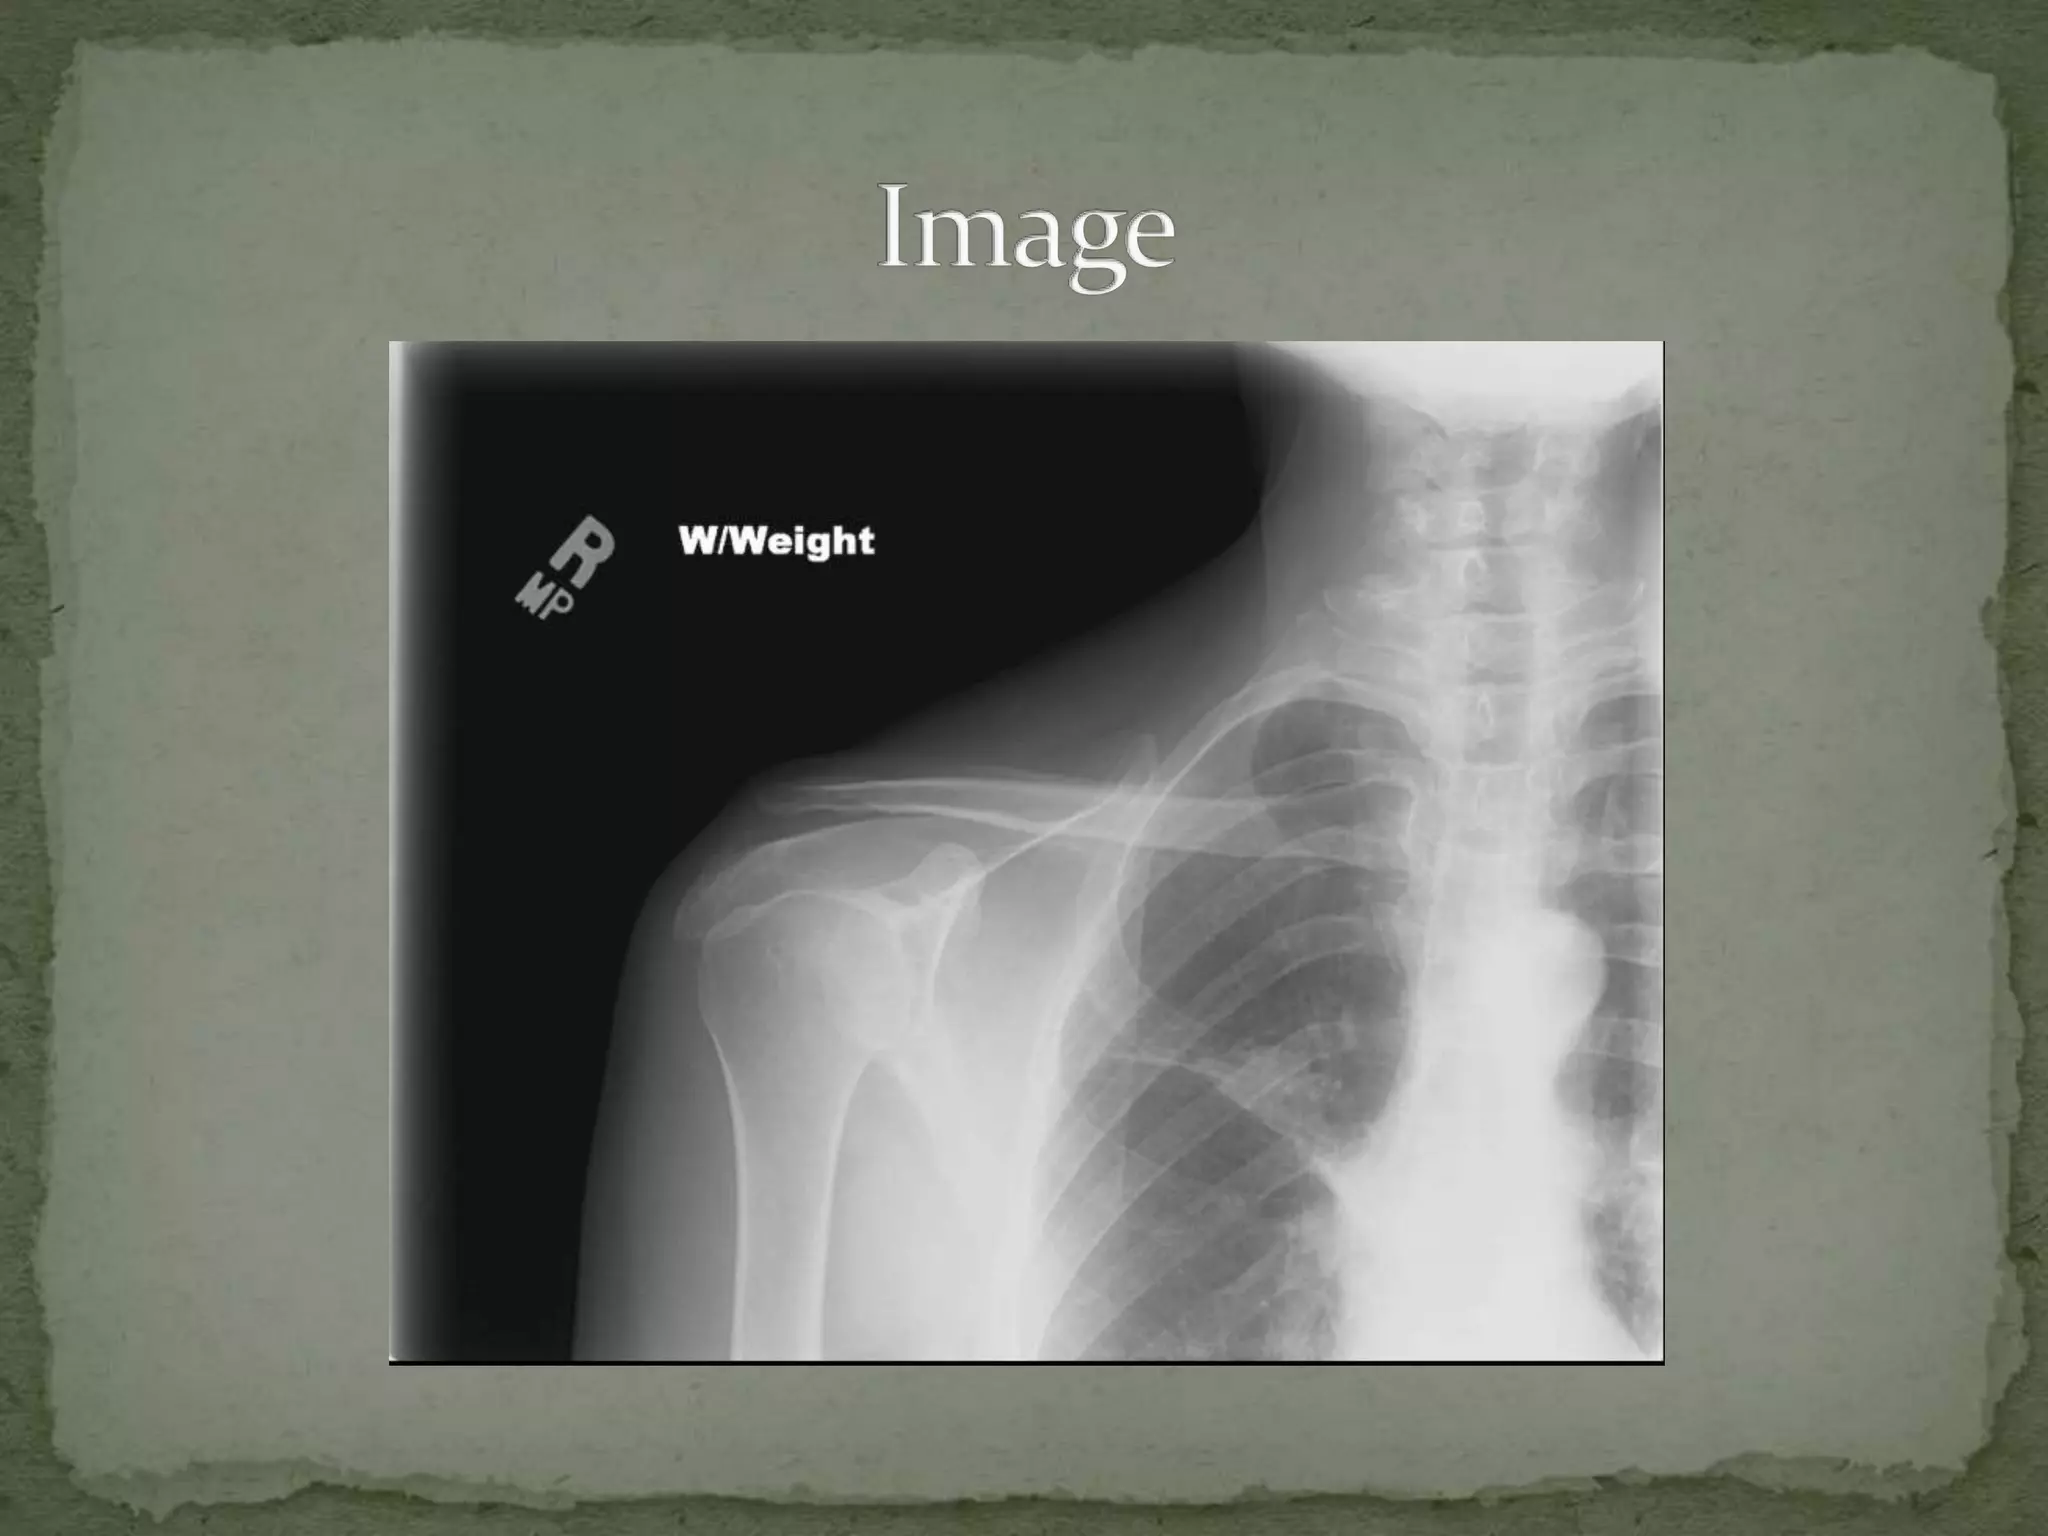

A 42-year-old man presented to the emergency department after being struck in the right shoulder with a baseball bat. On exam, he refused to move his shoulder due to pain and tenderness over the top of the shoulder. Imaging showed widening of the acromioclavicular joint space, indicating an AC joint separation. The separation was likely a Type III injury, with a complete tear of the AC and coracoclavicular ligaments and separation of the AC joint, requiring internal fixation surgery to repair the injury.